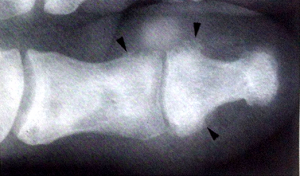

Η χρόνια ψωριασική αρθρίτιδα προκαλεί συχνά χαρακτηριστικές ακτινολογικές βλάβες, ικανές να τη διαφοροποιήσουν από τις άλλες πολυαρθρίτιδες. Ωστόσο σε αρκετές περιπτώσεις η διαφορική διάγνωση καθίσταται αδύνατη, ιδίως στα πρώιμα στάδια της νόσου. Βασικές χαρακτηριστικές ακτινολογικές βλάβες των αρθρώσεων στην ΨΑ (εικ.1) είναι:

| 1. | Η διαβρωτική αρθρίτιδα με συνοδό παραγωγή νέου οστού (proliferative erosions) |

| 2. | Η συχνή απουσία παραρθρικής οστεοπενίας |

| 3. | Το οίδημα των μαλακών μορίων και η περιοστική αντίδραση |

| 4. | Τα παρασπονδυλικά ασύμμετρα οστεόφυτα |

| 5. | Η ασύμμετρη ιερολαγονίτιδα |

| 6. | Οι χρόνιες πυρωτικές – ακρωτηριαστικές (καταστροφικές) μορφές |

Βασικά ακτινολογικά χαρακτηριστικά της ΨΑ: 1: έκδηλο παραθρικό οίδημα, 2: απώλεια της μεσάρθριας σχισμής, 3: διαβρώσεις του οστικού φλοιού (παριφών), 4: χνώδης περιοστίτιδα και 5: οστεοφύτωση.

1. Διαβρωτική αρθρίτιδα: Συχνά χαρακτηριστικά ευρήματα είναι οι αρθρικές διαβρώσεις, η διεύρυνση του μεσαρθρίου διαστήματος και η υποχόνδρια οστική σκλήρυνση6. Η συνοστέωση είναι λιγότερο συχνή συγκριτικά με την ΑΣ. Οι διαβρώσεις δείχνουν προτίμηση στις άπω φαλαγγικές αρθρώσεις και ειδικά στο μεγάλο δάκτυλο του ποδιού7. Οι διαβρωτικές αλλοιώσεις είναι ασύμμετρες, ακόμη και πολύ καιρό μετά την εμφάνιση της αρθρίτιδας, σε αντίθεση με τις διαβρώσεις στη ρευματοειδή αρθρίτιδα (ΡΑ). Στένωση του μεσαρθρίου διαστήματος μπορεί να μη συμβεί ποτέ στην ΨΑ. Οι διαβρώσεις αντιρροπούνται από παραγωγή νέου οστού στα όρια των φαλαγγικών αρθρώσεων και πολύ περισσότερο γύρω από τις διαβρώσεις της πτέρνας, όπου επεκτεινόμενες σχηματίζονται μεγάλες, ανώμαλες, χνουδωτές (fluffy), επώδυνες άκανθες. Τέτοιου είδους αλλοιώσεις είναι ακόμη πιο συχνές στο σύνδρομο Reiter, ενώ είναι σπάνιες στη ΡΑ (εικ.2). Προφανώς οφείλονται στην ενθεσίτιδα, δηλαδή στη φλεγμονή των σημείων περιοστικής πρόσφυσης των αρθρικών θυλάκων, των συνδέσμων και των τενόντων στα οστά. Οι διαβρώσεις της ΨΑ διαφέρουν από αυτές άλλων αρθρίτιδων, γιατί δεν έχουν σαφή αλλά «θαμπά και ξεφτισμένα» όρια και από αυτές εκφύονται «τούφες» περιοστίτιδος (βαμβακόμορφη ή χνοώδης περιοστίτιδα)8. Οι βαριές και χρόνιες μορφές συχνά συνδυάζονται με οστική αγκύλωση και πυρωτική (καταστροφική) αρθρίτιδα. Στα αρχικά ωστόσο στάδια η αρθρίτιδα δεν έχει διαβρωτικό χαρακτήρα.